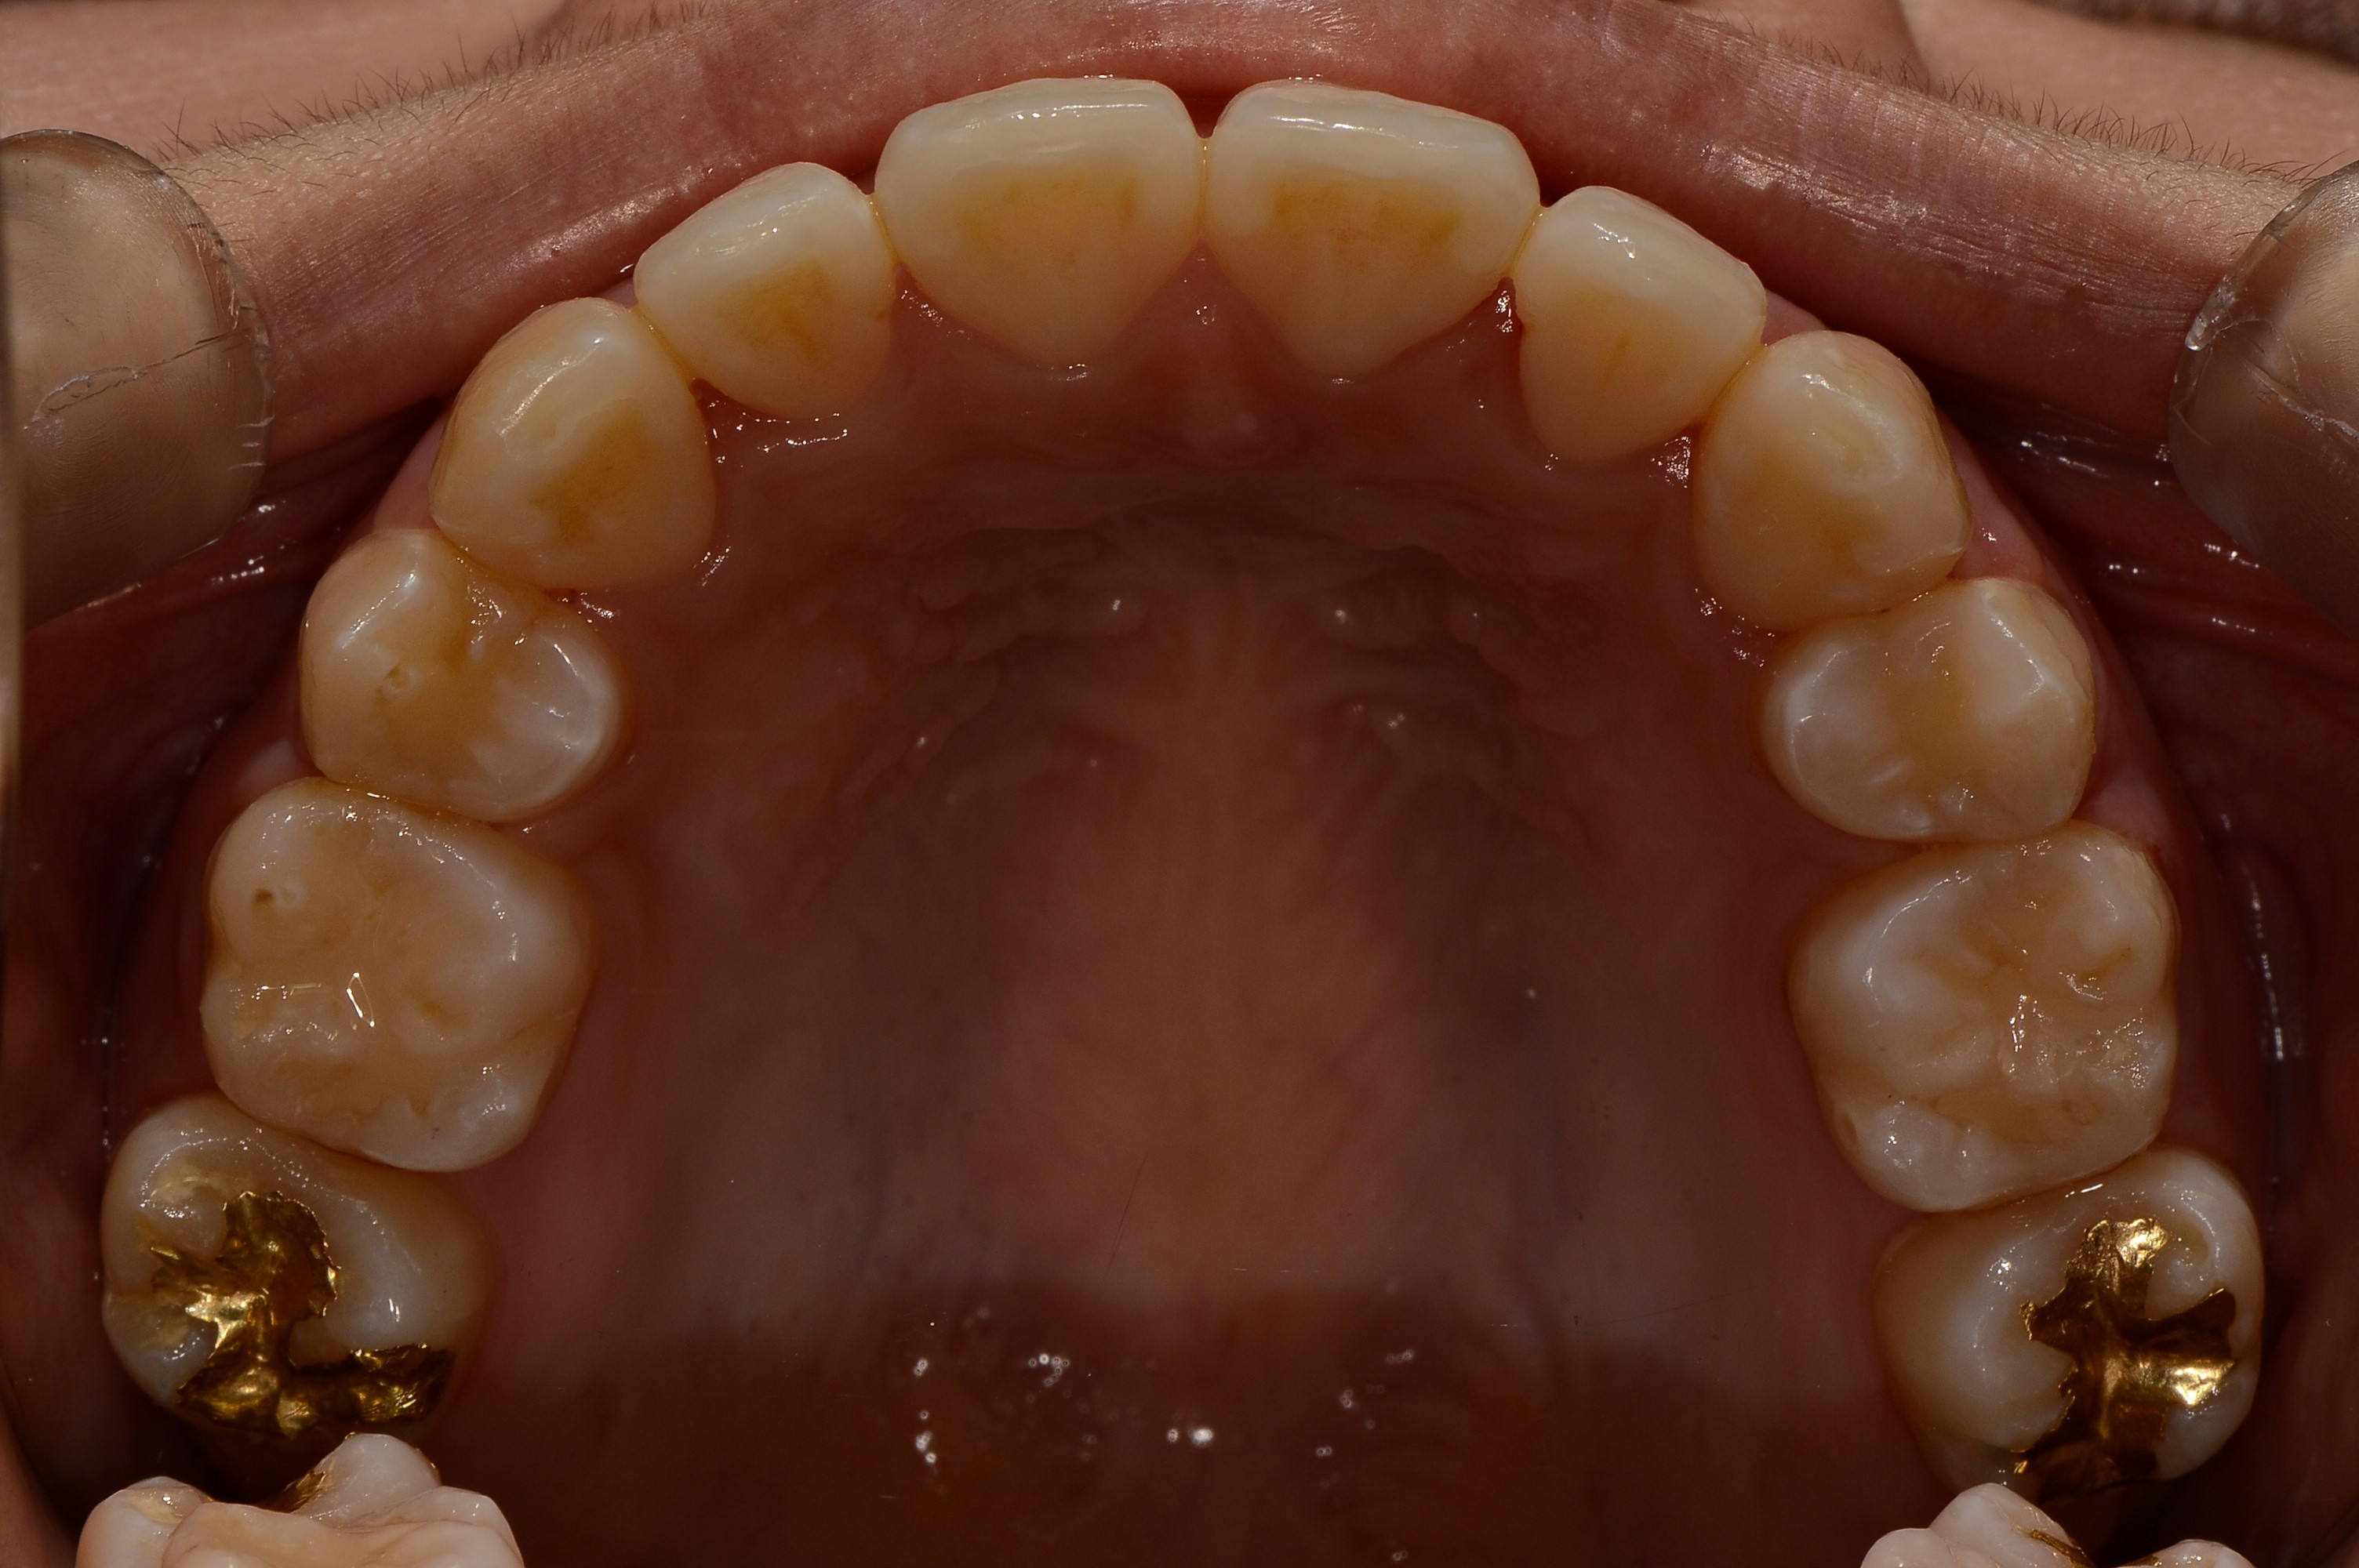

치료 전 사진입니다.